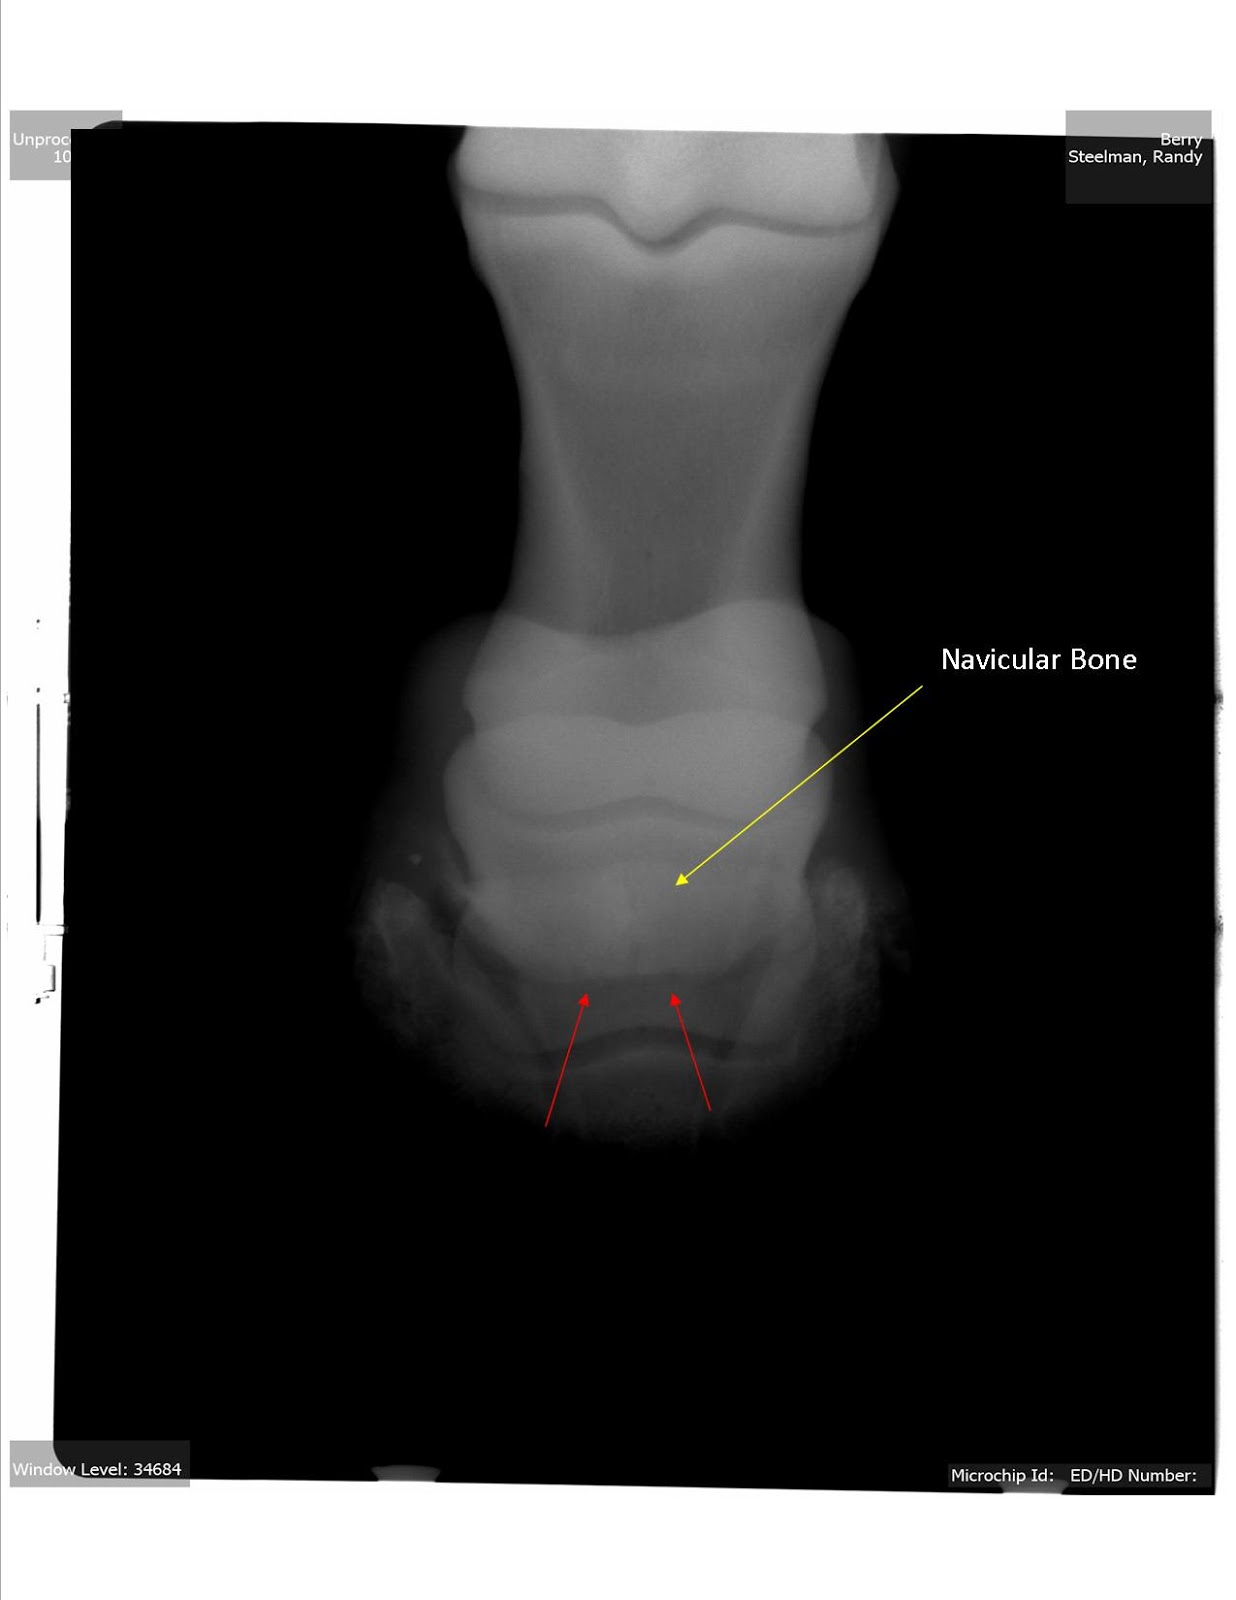

Horse Navicular X Ray . radiographs (x rays) are still important for examining the hoof’s bony structures and changes that are occurring. accurate radiographic evaluation of the navicular bone depends on a radiograph that is properly positioned and exposed and on a foot that is free of distracting artifacts. Many horses have pain in the heel region, which can be elicited by hoof testers. Radiographs will show any degenerative. However, researchers have found in. Abnormalities in the navicular bone navicular in horses relates to problems associated with the navicular bone in the horse’s hoof and is a common diagnosis for lameness in the front foot. Proper preparation for navicular radiography is similar to that for the distal phalanx, as discussed in chapter 23. a study looking at 72 horses that underwent mri for recent onset of navicular syndrome but without abnormalities detected on radiographs found the following: diagnostics involved in determining whether a horse has navicular syndrome include: Most horses show marked improvement in lameness with a palmar digital nerve block.

diagnostics involved in determining whether a horse has navicular syndrome include: radiographs (x rays) are still important for examining the hoof’s bony structures and changes that are occurring. navicular in horses relates to problems associated with the navicular bone in the horse’s hoof and is a common diagnosis for lameness in the front foot. Most horses show marked improvement in lameness with a palmar digital nerve block. Radiographs will show any degenerative. accurate radiographic evaluation of the navicular bone depends on a radiograph that is properly positioned and exposed and on a foot that is free of distracting artifacts. Abnormalities in the navicular bone Many horses have pain in the heel region, which can be elicited by hoof testers. However, researchers have found in. Proper preparation for navicular radiography is similar to that for the distal phalanx, as discussed in chapter 23.